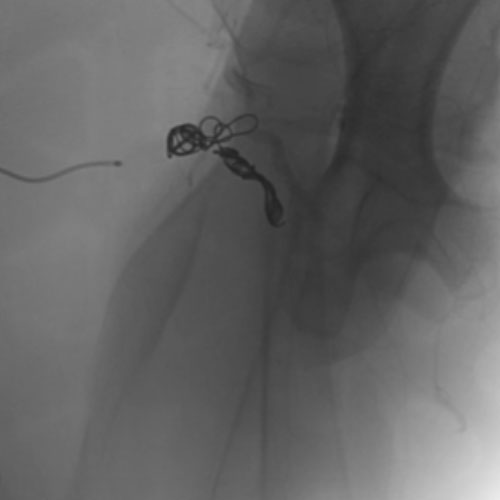

Embold Fibered Coil shown in left internal femoral artery Ruby Standard Coil shown in left internal femoral artery

Left Internal Femoral

Artery

5 Ruby Standard 6x20

Embold Fibered Coil shown in right internal femoral artery Embold Fibered Coil shown in right internal femoral artery

Right Internal Femoral

3 Embold Fibered Coil 6x20